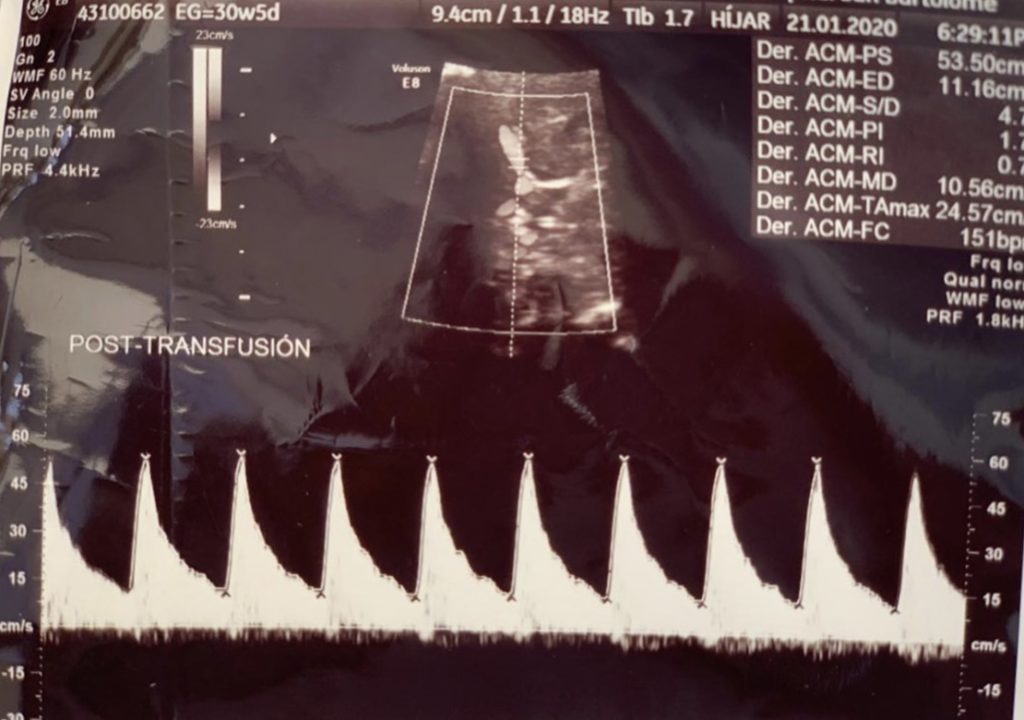

Pues bien, ese día llegó, uno de los lunes que vino la paciente los valores de PS para las 30 semanas que tenía habían pasado a un rango de anemia moderada y era el momento de intervenir o el nene, indefectiblemente fallecería.

Luego de ello se procedió a la TRANSFUSIÓN INTRAUTERINA: inyección de sangre de donante grupo O Rh negativo, se calculó 46cc según el aplicativo del Perinatology.